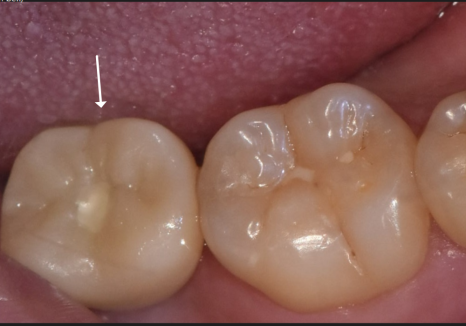

환자분께서는 왼쪽 위 어금니(#26)에 난

구멍이 점점 커지는 걸 느끼면서도,

극심한 치과 공포증 때문에 수년간

내원을 미루셨다고 해요.

그동안 불편함을 참고 주로

오른쪽으로만 식사를 하셨는데,,

이제는 믿었던 오른쪽 아래 어금니(#47)까지

흔들리기 시작하자 더는 버틸 수 없어

저희 치과를 찾아주셨어요.

입안을 보니 이미 치아가 충치로 인해

많이 삭아 있었습니다.

방사선 사진상으로는 상태가 더 심각했는데요.

보이는 것보다 충치가 훨씬 깊게 파고들어,

마치 겉면만 간신히 남고

속은 텅~비어버린 상태였어요.